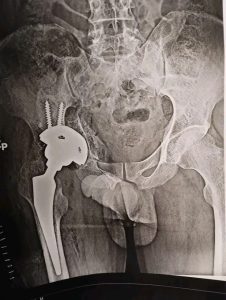

ومن جانبه قال الدكتور مجدي القاضي انه تم تقييم الحالة الصحية لأحد المرضي الأشقاء من أهالى غزة، ويبلغ من العمر 41 عاما ويعانى من خلع بمفصل الحوض منذ ٦ شهور، وعلى الفور تم إجراء العملية الجراحية للمريض وتركيب مفصل حوض كامل، مضيفاً أن ادارة المستشفي تولي اهتمام كبير ورعاية مستمرة لجميع مصابي غزة منذ ان وطأت اقدامهم داخل المستشفي الجامعي، وذلك تنفيذاً لتوجيهات الدكتور حسان النعماني رئيس الجامعة واهتمامه البالغ بمتابعته المستمرة لمستوي التحسن لحالتهم الصحية.

وقال الدكتور عبدالرحمن الشيخ انه تم استقبال المريض بقسم العظام وعمل الفحوصات والتحاليل المخبرية والاشاعات اللازمة وعلي الفور تم تشكيل الفريق الطبي المعالج الذي اجري العملية الجراحية ببراعة كبيرة، حيث بلغت تكلفة المفصل ٨٥ الف جنيه كتبرع من قسم العظام، موضحاً ان الفريق الطبي تكون من الدكتور ياسر عثمان استاذ جراحة العظام، الدكتور حسام حسنى والدكتور محمد شحاتة والدكتور عبدالرحمن بهاء مدرسين مساعدين بقسم العظام، الدكتور اسلام النحاس والدكتور مصطفى عبداللاه والدكتور يوسف راضى معيدين بقسم العظام، والدكتور على الشيخ والدكتور محمد جمال نواب سنيور بقسم العظام، بينما ضم فريق التخدير بقيادة الدكتور فوزي عباس كلاً من، الدكتور احمد عزمى مدرس مساعد تخدير، والدكتور عمرو عبد الصبور و الدكتورة ريهام رجب نواب سنيور بالقسم، وشكر خاص لفريق الهيئة التمريضية علي مابذلوه لإنجاز هذا العمل الانساني الكبير.